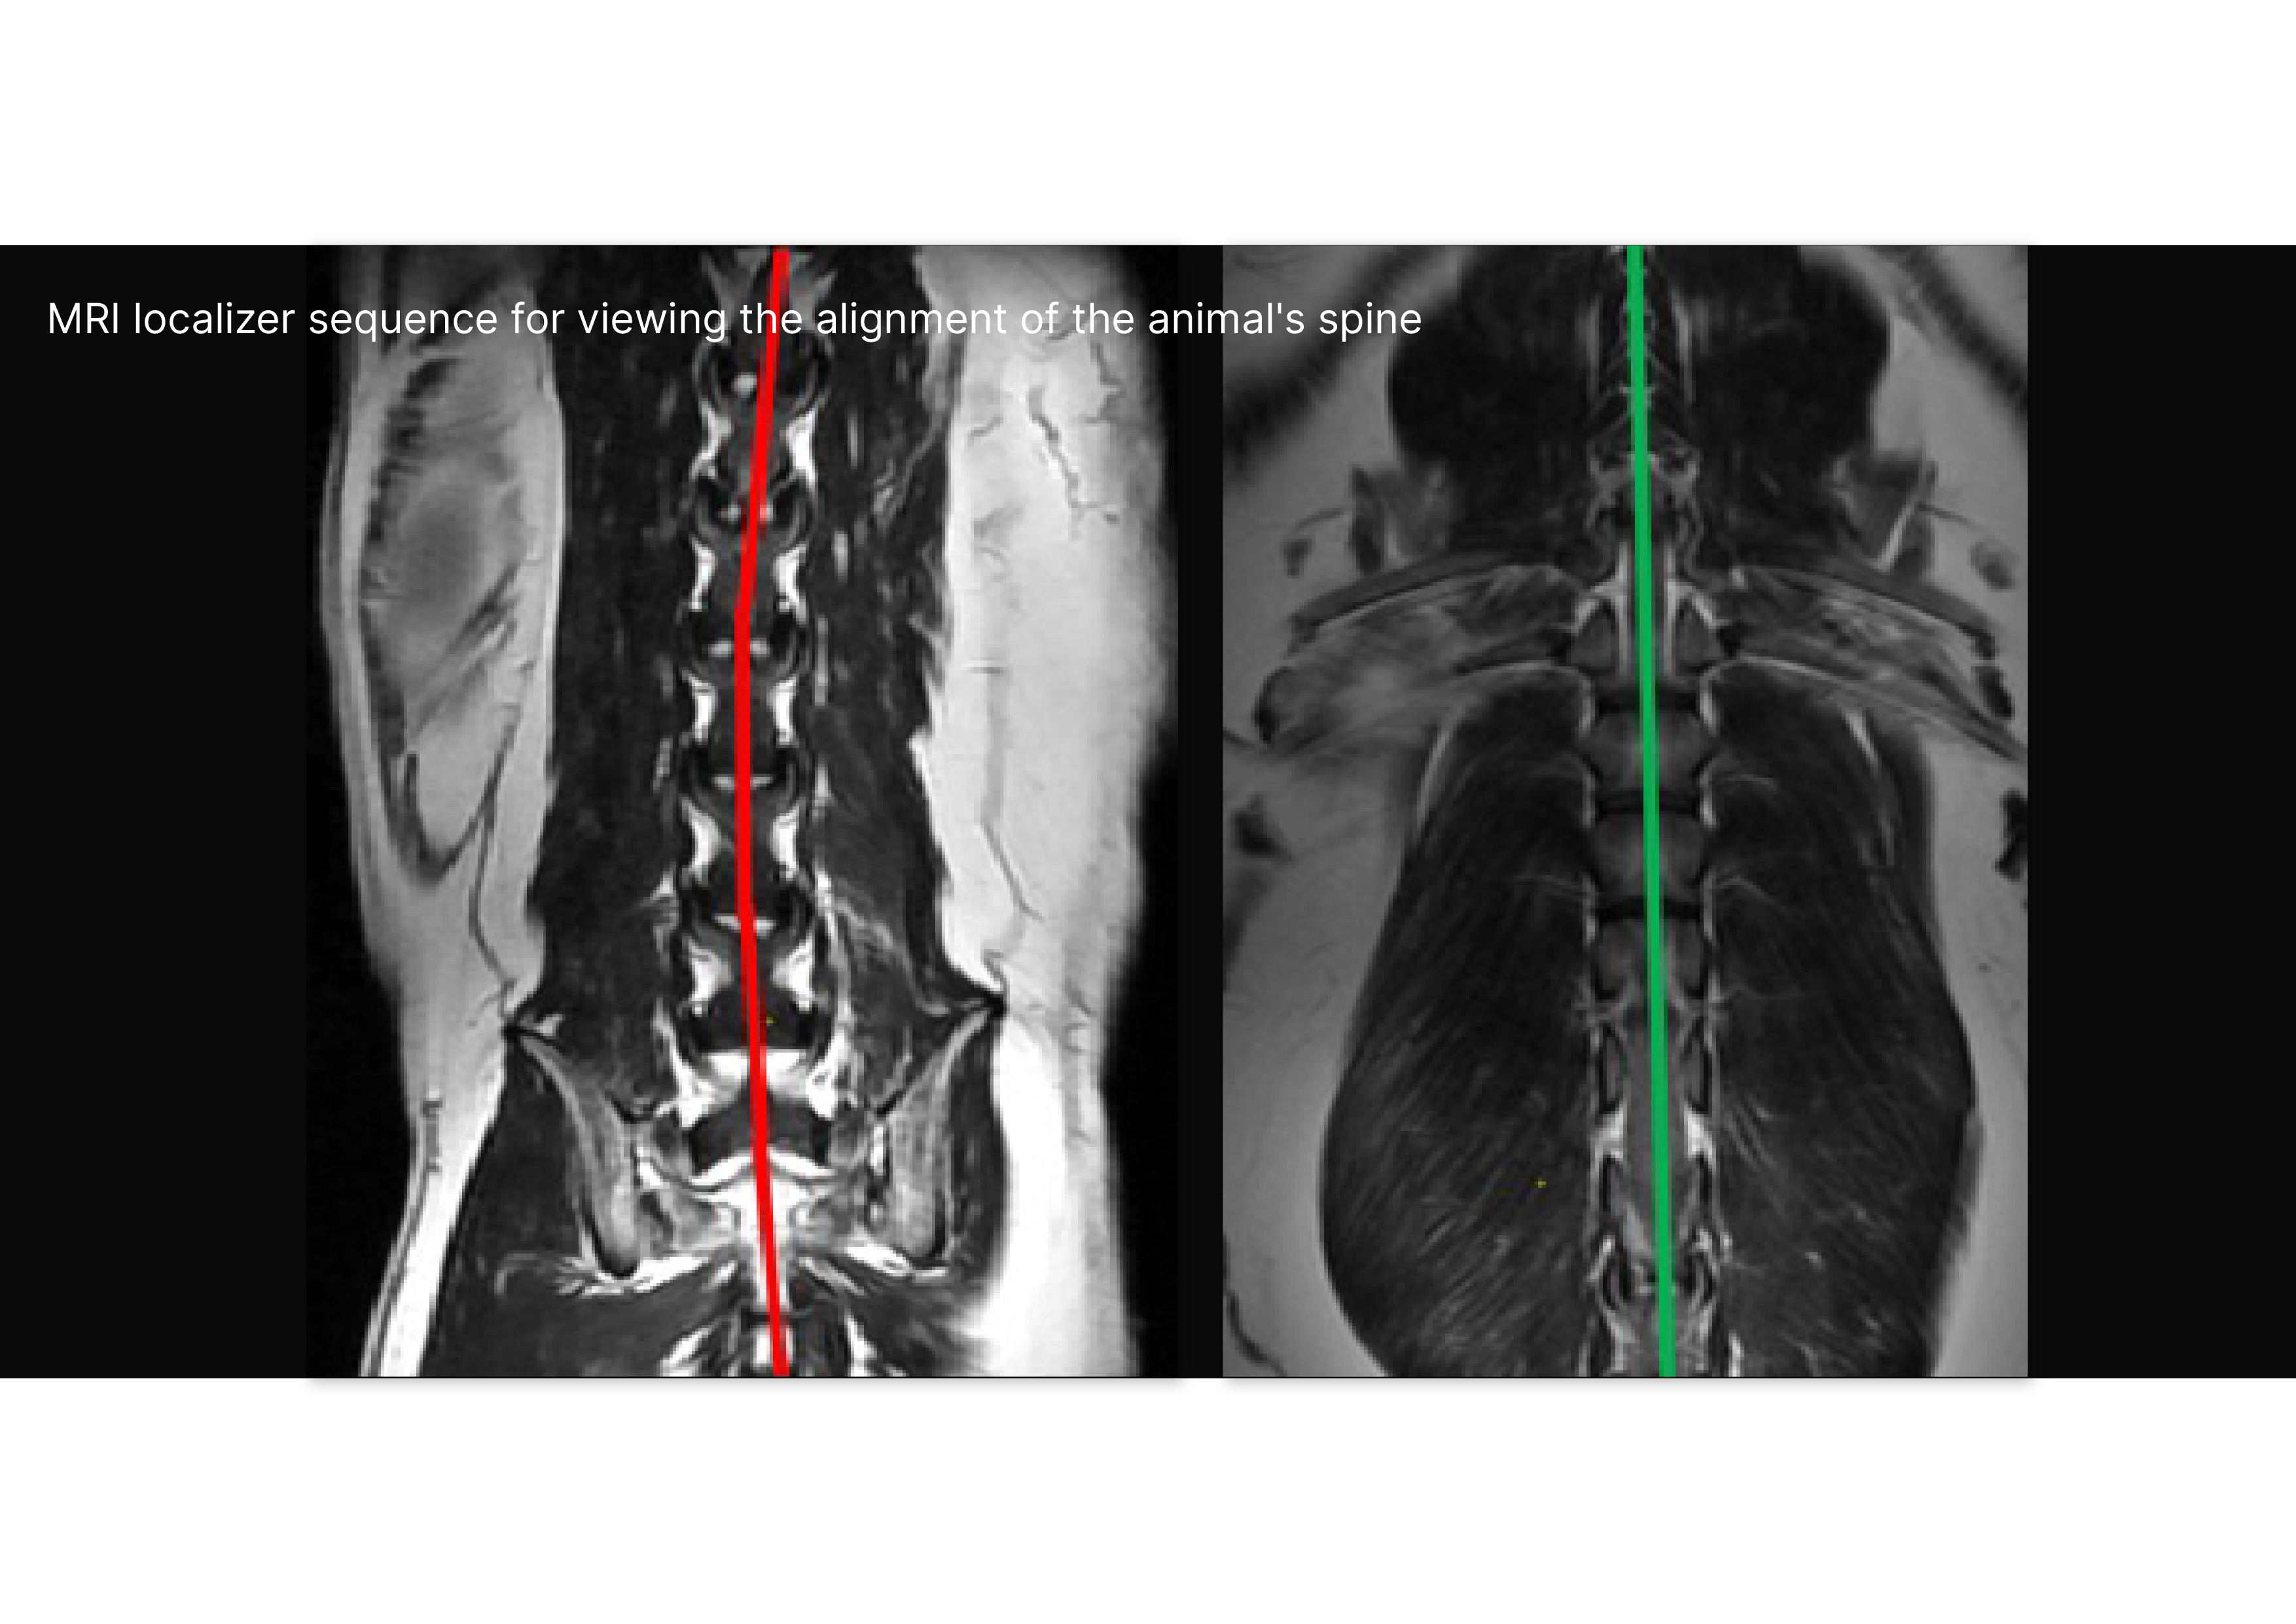

A plug-and-play solution engineered to elevate any MRI, CT, and CBCT system to the realities of animal morphology.